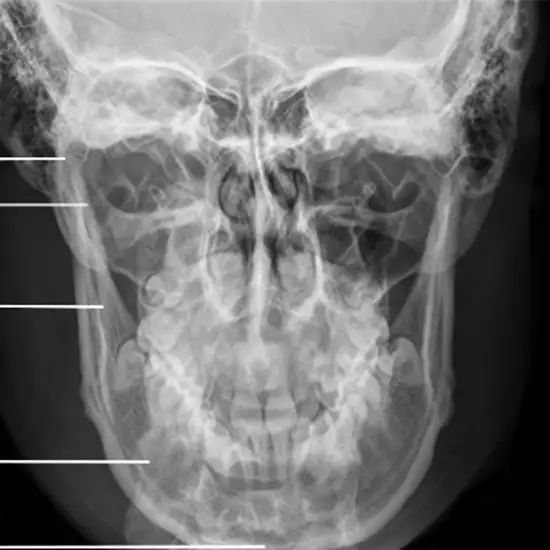

X-RAY MANDIBLE PA VIEW PROCEDURE

X-ray mandible PA View is used to detect

• Mandibular menti fracture

• Medial and lateral displacement of skull fracture

• Neoplastic changes

• Paget’s diseases

• TM joints

• Mastoids sinus

Patient positioning

• The patient is erect.

• The patient’s forehead is placed against the image detector and allows the nose to be in contact as well.

• Mid-sagittal plane is the right angle to the cassette.

Central Ray

• Centre ray is 2 cm below the TM joints

• Mid-sagittal plane is perpendicular to the IR/ Cassette.